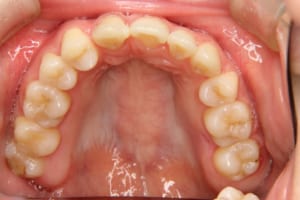

• Before

治療前